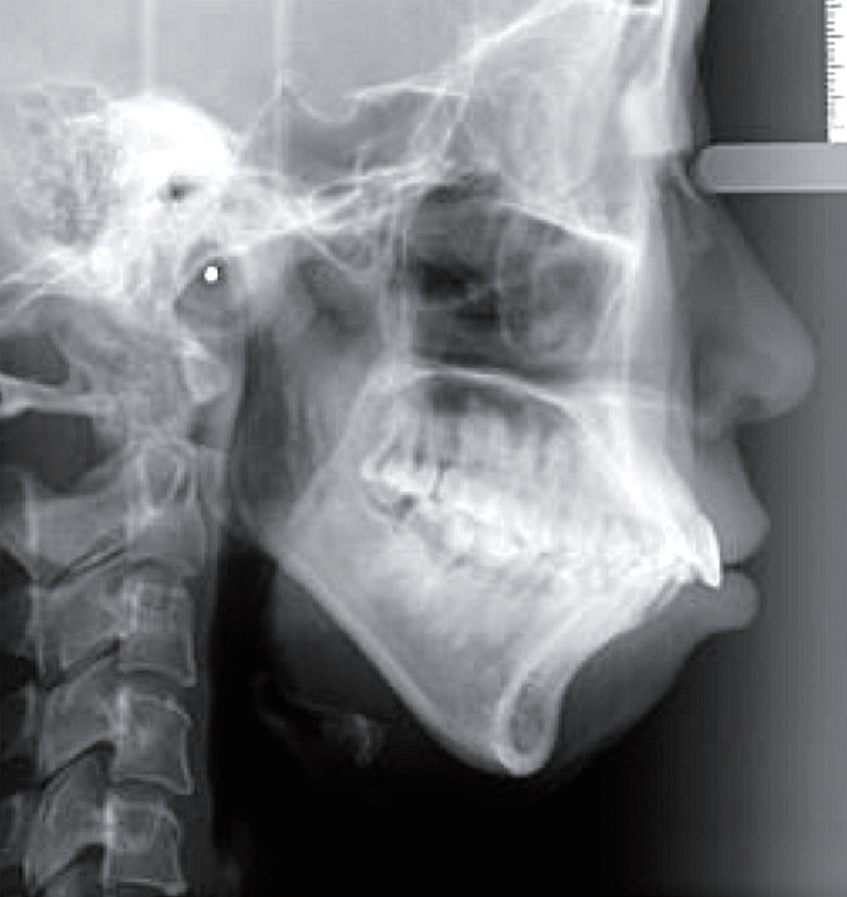

这位女士主诉自己嘴凸没有下巴, 综合牙片检查可见高角、下颌后缩、上颌前凸,前牙唇倾,III度深覆盖,牙弓狭窄,下前牙拥挤不齐。

考虑到嘴凸、下巴后缩严重,想要拔牙让下巴导出多一些,根据女士的要求和具体情况,设计了拔牙矫正方案,使用舌侧矫正器。